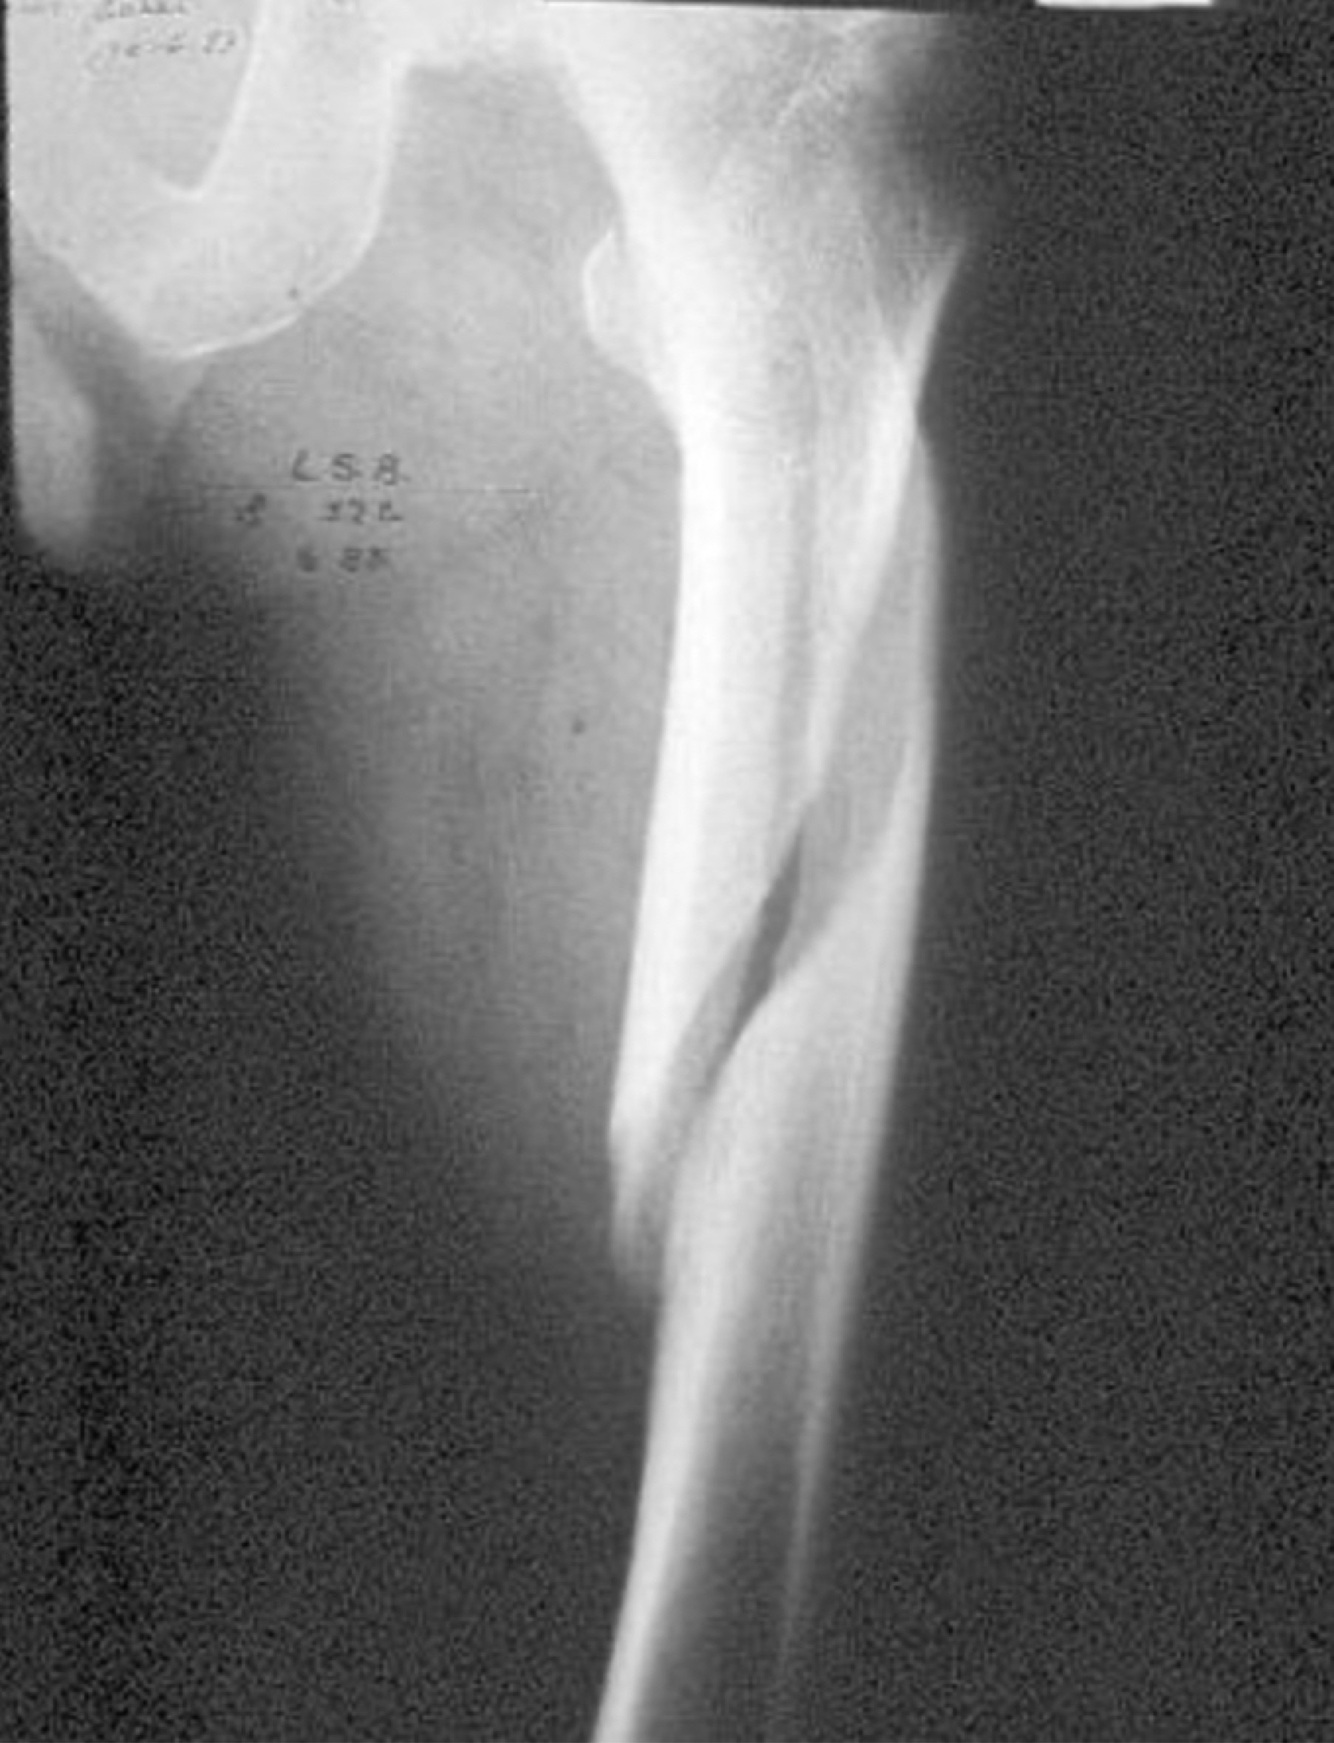

Un trabajador dominante de la mano izquierda de 22 años sufre la siguiente lesión como resultado de una caída de una escalera. Cual de las siguientes aseveraciones es correcta: Pregunta 6 opciones: Presenta inminencia de exposicion El mejor tratamiento para este caso es el conservador Lo primero que hay que hacer es pedir interconsulta al traumatólogo El riesgo de una lesión vascular es bajo

Presenta inminencia de exposicion

Un hombre de 35 años con la mano derecha como dominante, se cae de una escalera y sufre la siguiente lesión. Cual de los siguientes enunciados corresponde a una indicación absoluta para cirugía Pregunta 7 opciones: Acortamiento de mas de 15mm Fractura patológica no desplazada Fractura Multifragmentada Tórax Inestable

Tórax Inestable